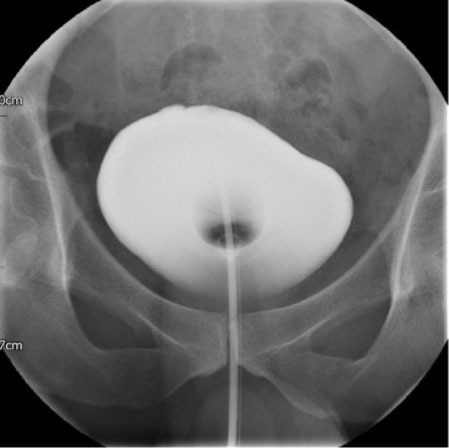

Figure 5: Cystogram demonstrating no urinary leak (Anterior view).

Share Image:

Unfortunately, due to a long waiting list for radiological procedures, the patient had a cystography a month later. No evidence of urinary leak was demonstrated (Figure 5 and Figure 6). The urethral catheter was eventually removed and he was able to pass urine adequately. A post-void bladder scan showed only 75 mL.